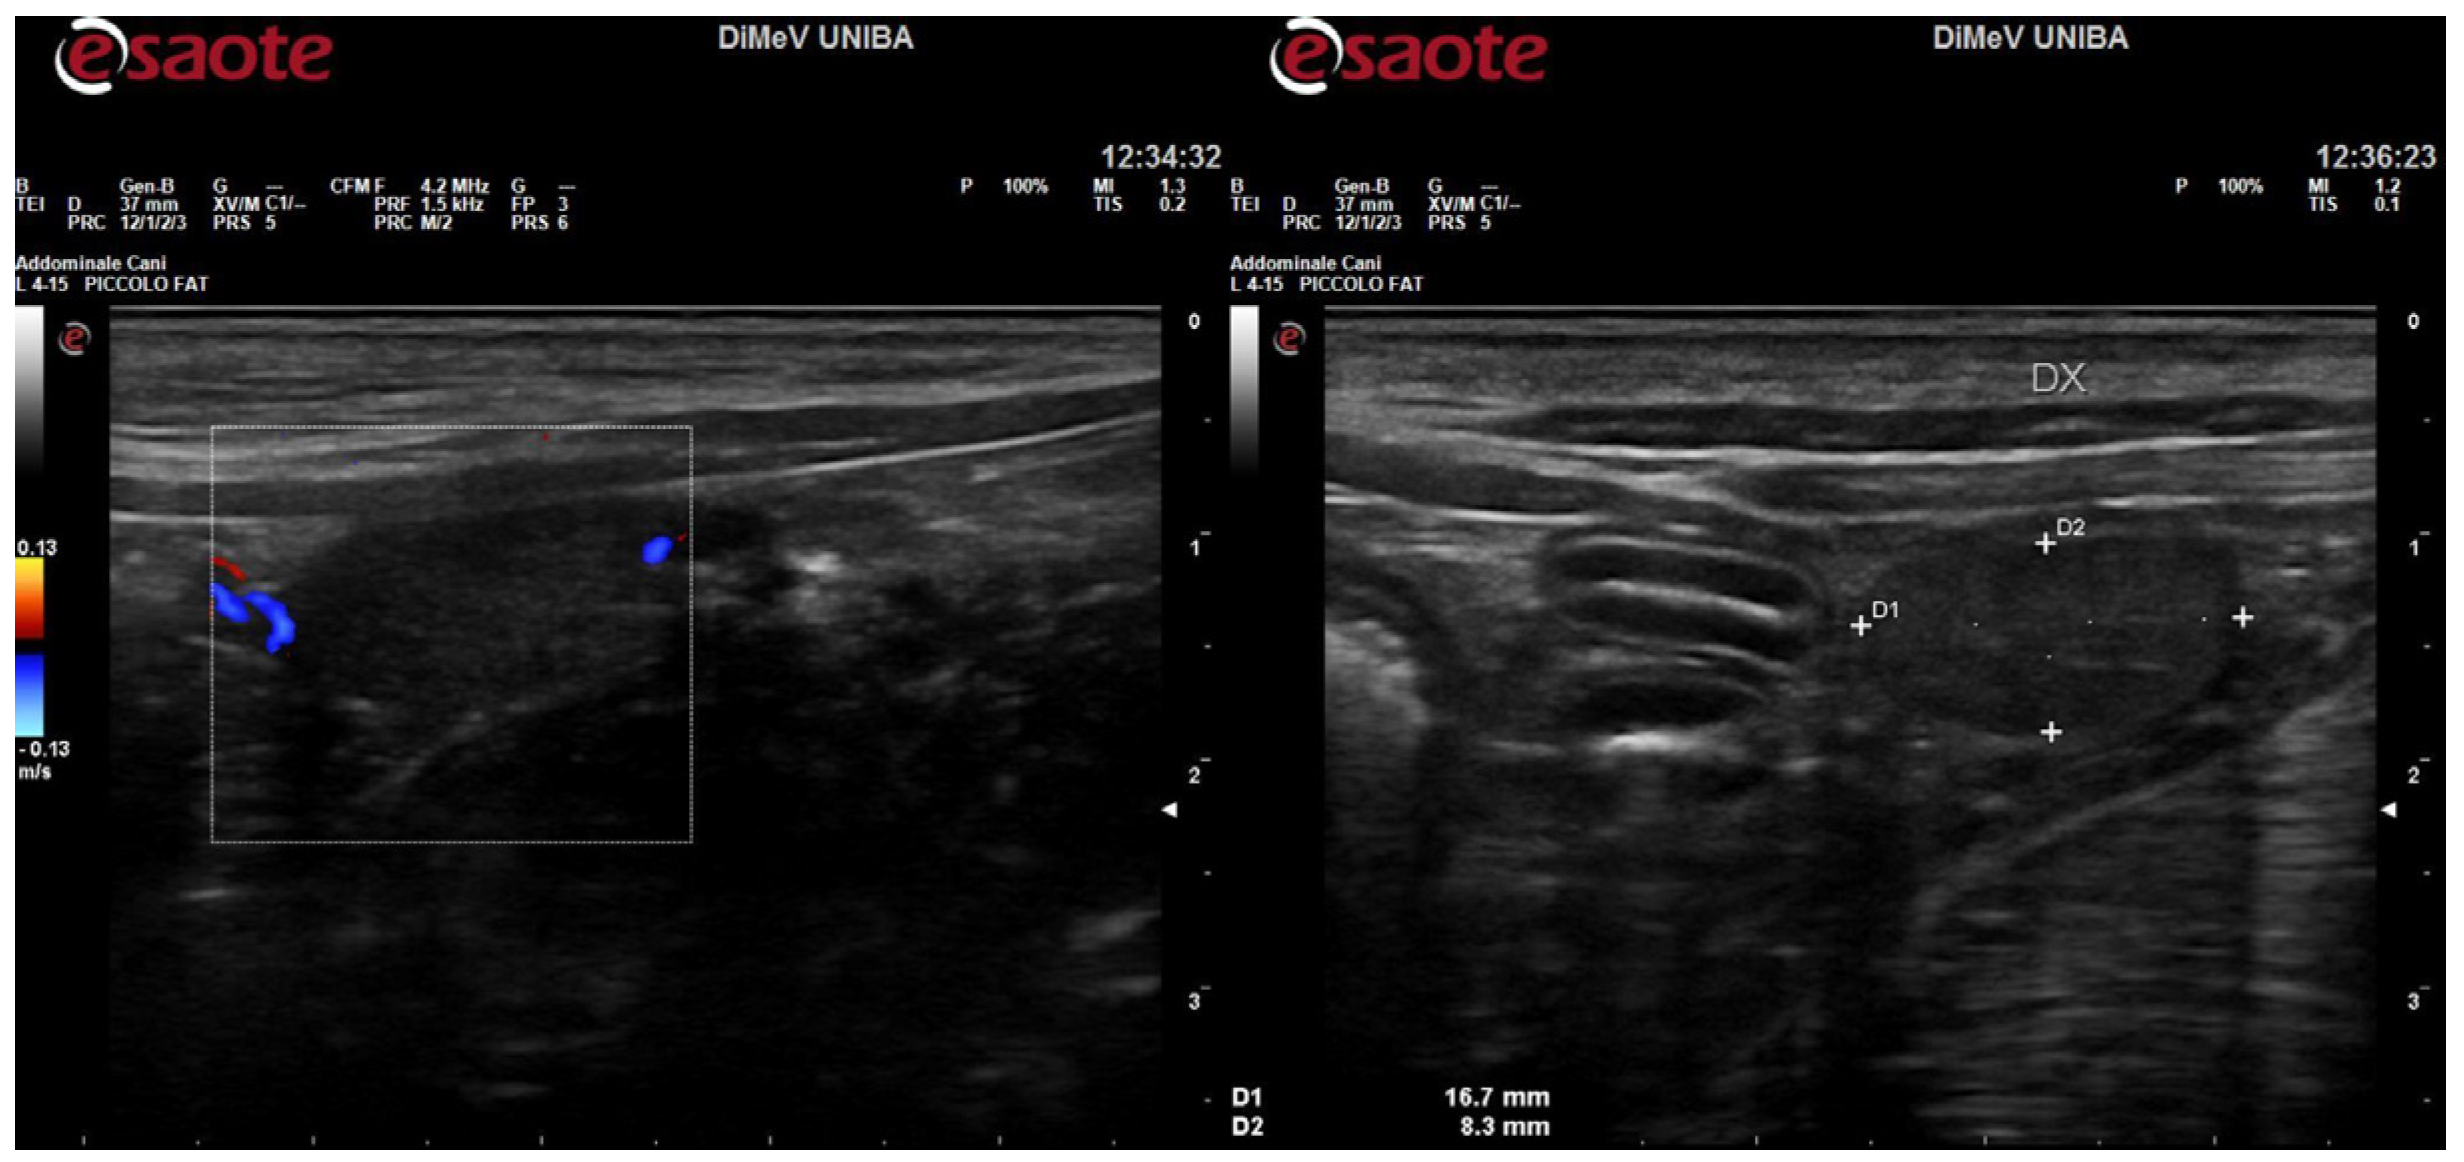

4.1. Clinical Characterization of Brutus